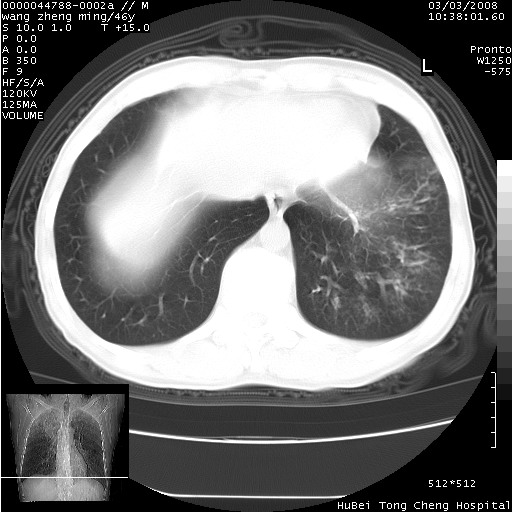

以下是引用卜一在2008-3-22 1:37:00的发言:[br]右肺实质性肿块,边缘不整,明显见毛刺征 分叶征及胸膜凹陷征,右上叶支气管明显变窄,远端散在的片状 斑片状实变影。另:左肺门较大肿块,支气管受累 变窄,远侧见阻塞性肺炎。纵隔内见肿大淋巴结。多考虑:右肺周围性肺癌伴左肺门 纵隔淋巴结转移!